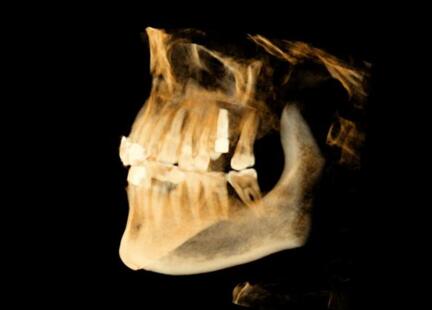

該系統(tǒng)用于口腔種植手術(shù)的術(shù)前計(jì)劃和術(shù)中引導(dǎo),通過對三維醫(yī)學(xué)影像的虛擬可視化應(yīng)用,采用專門的種植手術(shù)方案規(guī)劃軟件在三維模擬環(huán)境中進(jìn)行合理的種植方案設(shè)計(jì),結(jié)合精確的紅外光學(xué)定位技術(shù),實(shí)現(xiàn)手術(shù)器械、醫(yī)學(xué)影像和人體空間位置的融合。整個(gè)手術(shù)過程系統(tǒng)實(shí)時(shí)呈現(xiàn)病人解剖結(jié)構(gòu),全程監(jiān)控種植位點(diǎn)、角度、深度,從而實(shí)現(xiàn)精確種植。

運(yùn)用計(jì)算機(jī)三維重建與可視化技術(shù),清晰展現(xiàn)患者口內(nèi)解剖結(jié)構(gòu),保證了復(fù)雜病例的成功率。

導(dǎo)航病例1:上前牙缺失

患者信息:年輕,女性

主訴:上前牙殘根拔除術(shù)后六周,要求種植修復(fù)

現(xiàn)病史:患者因牙列不齊行正畸治療,約六周前正畸結(jié)束,并拔除上前牙殘根,要求種植修復(fù)。

檢查:21牙缺失,缺牙區(qū)牙齦狀況良好,無紅腫潰瘍,唇側(cè)牙槽骨豐滿度不足,近遠(yuǎn)中及齦頜距離可,原有過渡義齒佩戴良好。上下前牙淺覆頜覆蓋。全口衛(wèi)生良好。

種植體選擇:3.3*12mm士卓曼骨水平種植體

導(dǎo)航病例2:左上后牙缺失

患者信息:55歲,男性

主訴:患者牙缺失半年余,現(xiàn)要求種植修復(fù)

26距25為3mm,26距27為4.71mm 26牙為4.10x11.50mm植體

術(shù)前種植體規(guī)劃